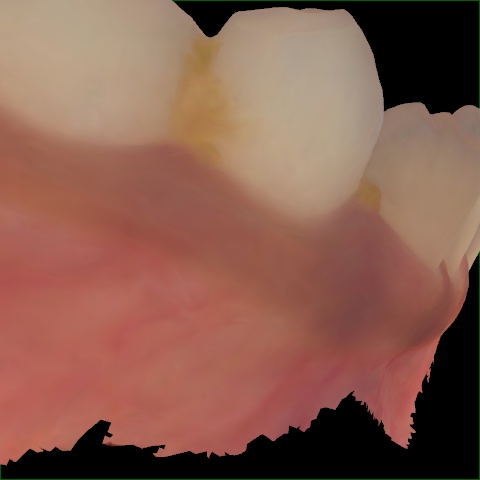

Image 245 / 255

NHD27230

Annotated as "Good"

Original Image Rendering Image